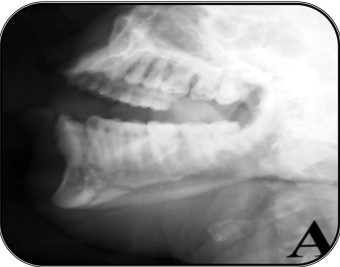

Extra-oral MultiDirectional Distractor: A Multi Uses Distractor